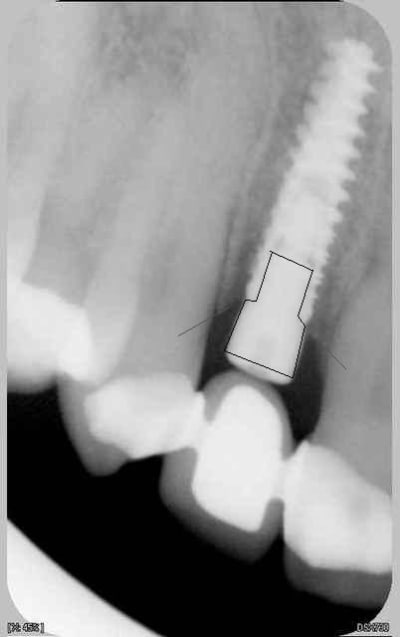

c'est des krestals? Ça n'a pas l'air dramatique sur la radio. Une petite caractérisation qui me parait logique vu la connexion.

On n'a pas les mêmes critères d'exigences. Perdre 4 mm d'os sur 12 soit 1/3.

Attends, sur ces radios t'as 4 mm de perte osseuse? Les vis de cicatrisation sont en place non? Je devine la jonction implant/vis et y a quasiment pas de perte sur tes dernières radio. Enfin je connais pas bien le krestal et la forme de la vis.

Je veux dire, elle est où la perte osseuse sur cette radio? Mais tu as raison, on ne doit pas avoir les même exigences.

Krestal dxzowc - Eugenol

La cratérisation est visible beaucoup plus haute: surtout au sondage. L'os que tu vois est en palatin, en vestibulaire, il n'y a plus rien sur cette même longueur.

Sur la molaire, tu ne vois rien aussi.